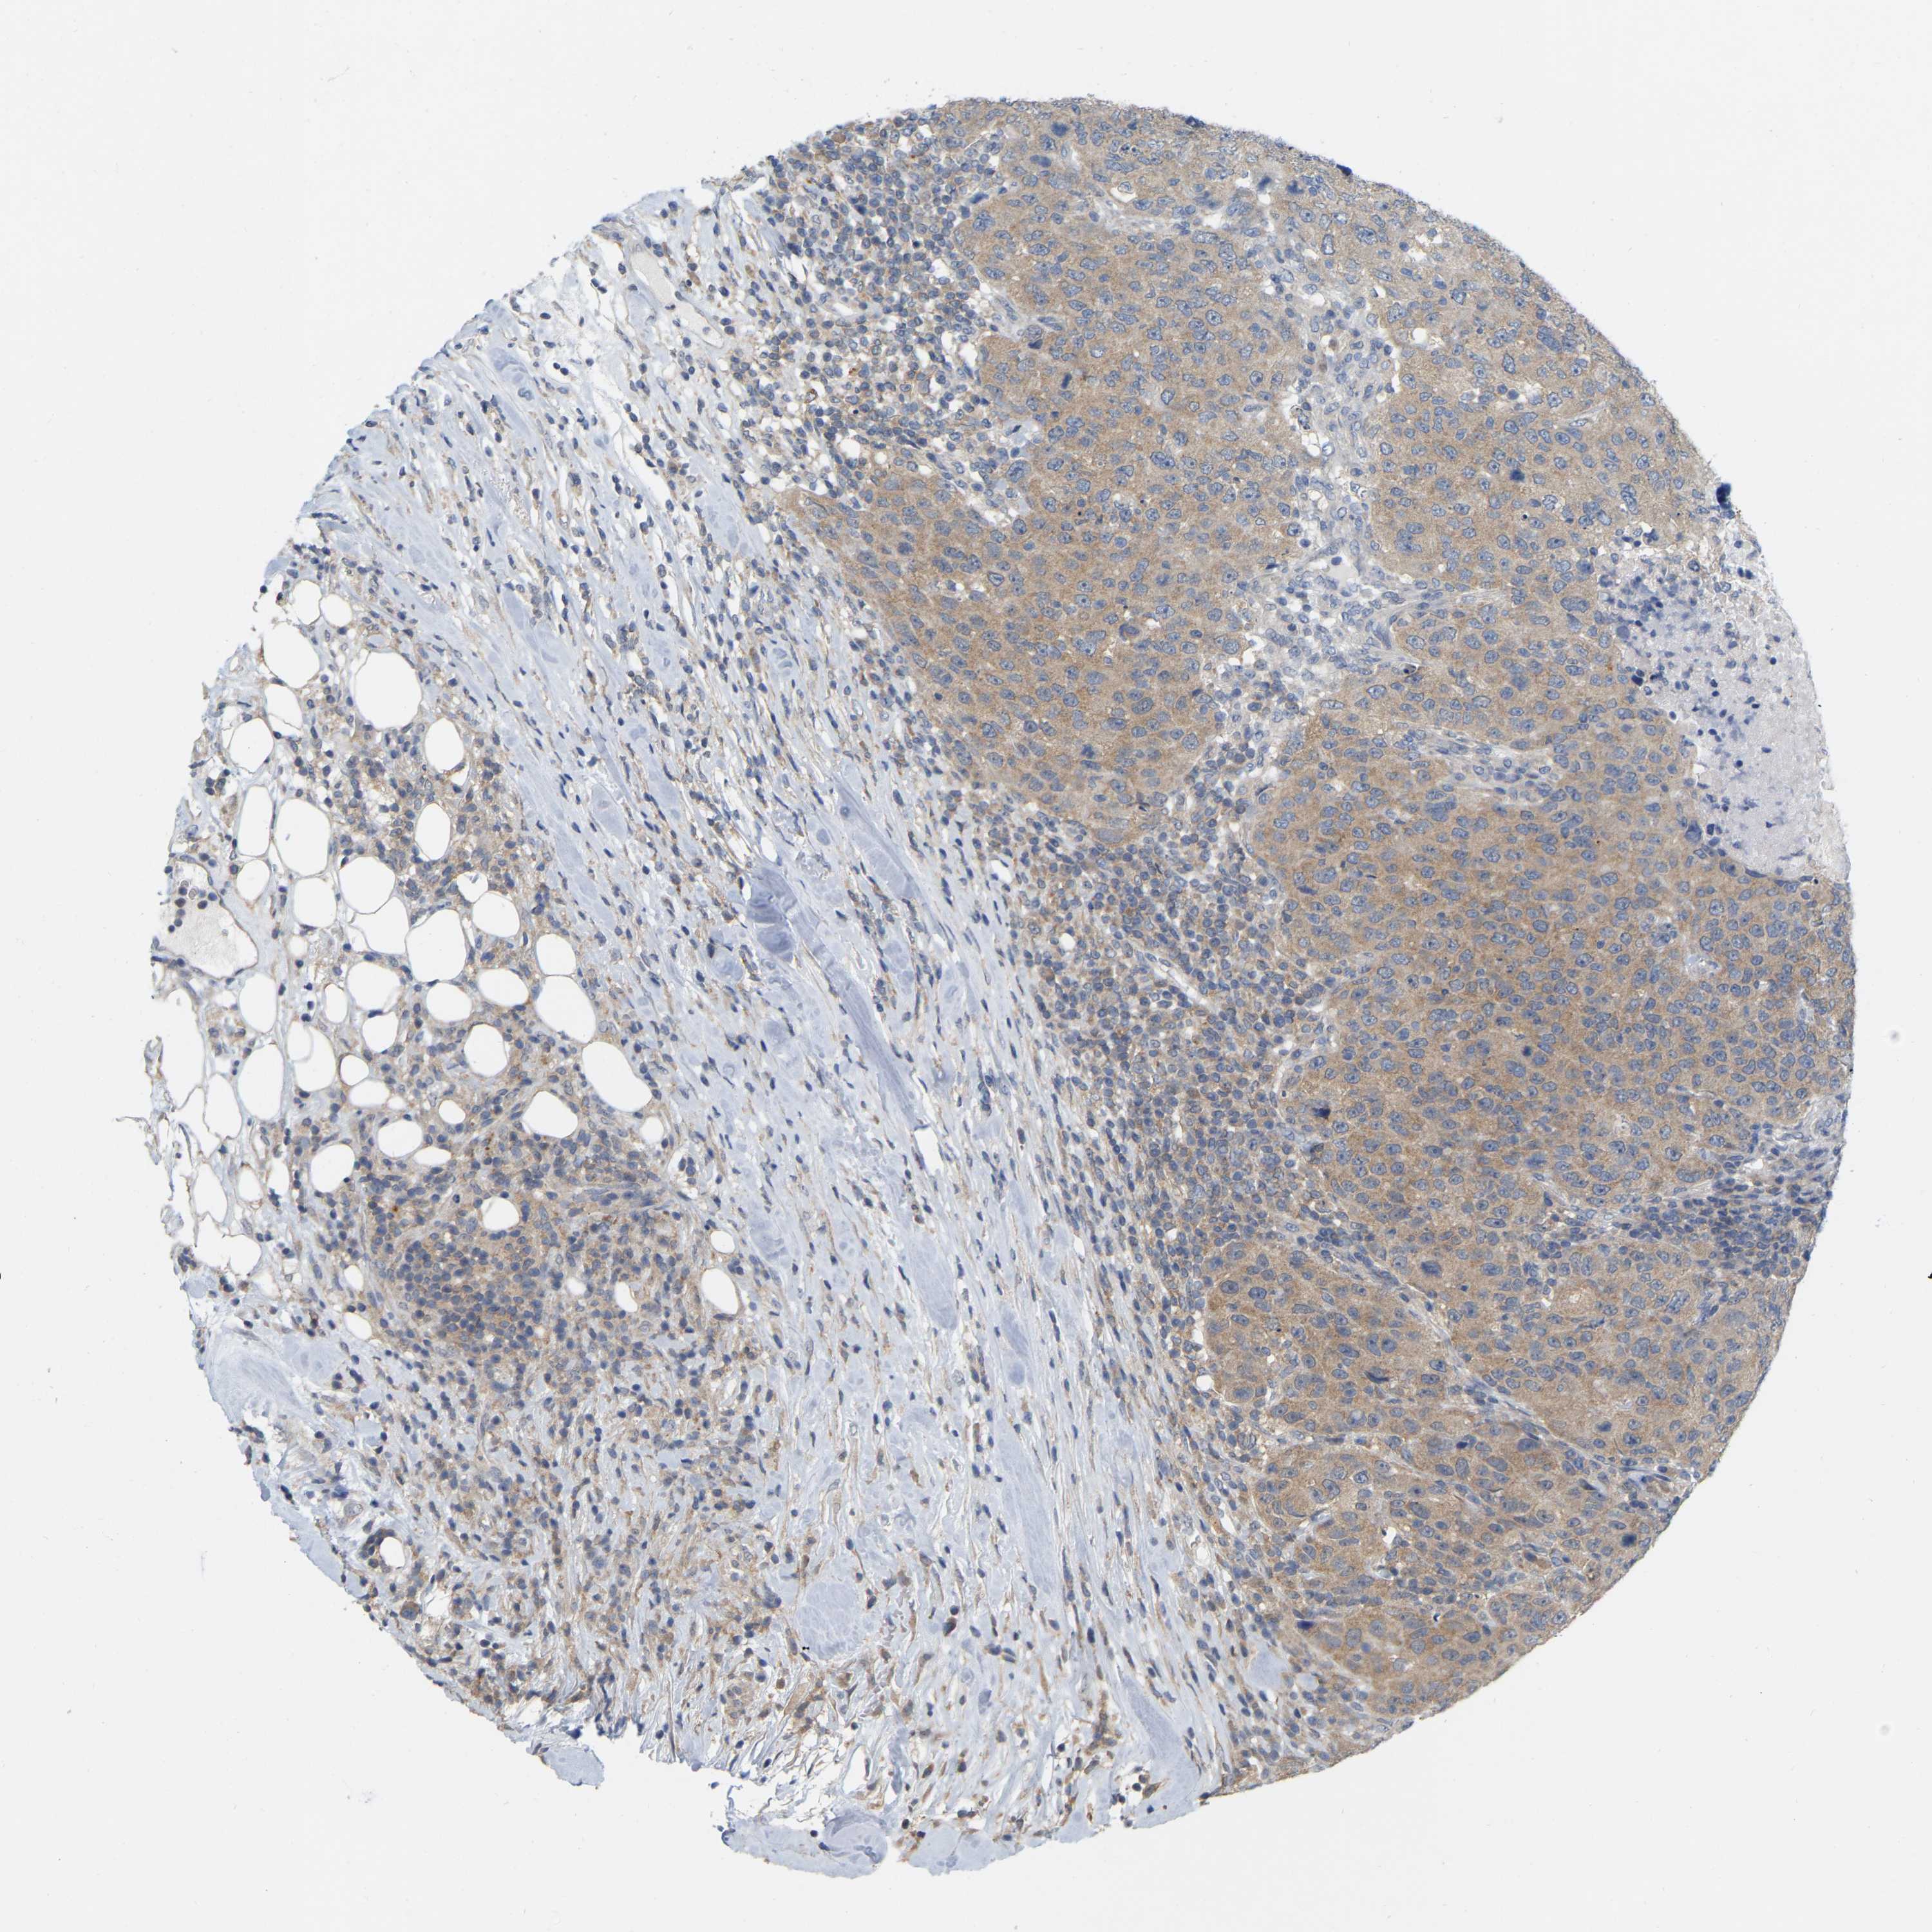

CANCER BREAST CANCER Show tissue menu

BRCA TCGA BRCA VALIDATION PROTEIN EXPRESSION

ANTIBODIES

AND

VALIDATION